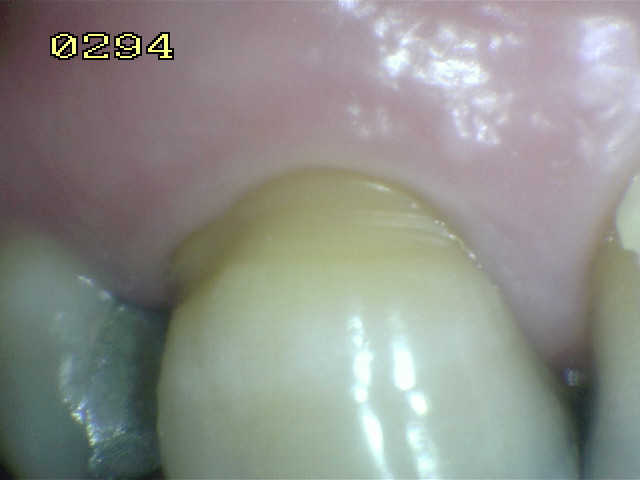

Código 0:

La

superficie de la raíz

no presenta ninguna

coloración

inusual

que lo distingue de

los alrededores o

las áreas adyacentes

de la raíz,

ni

exhibir un

defecto de la superficie,

ya sea en

la unión cemento-esmalte

o totalmente en

superficie de la raíz.

tiene un contorno

anatómico

natural. Ver imagen inferior.